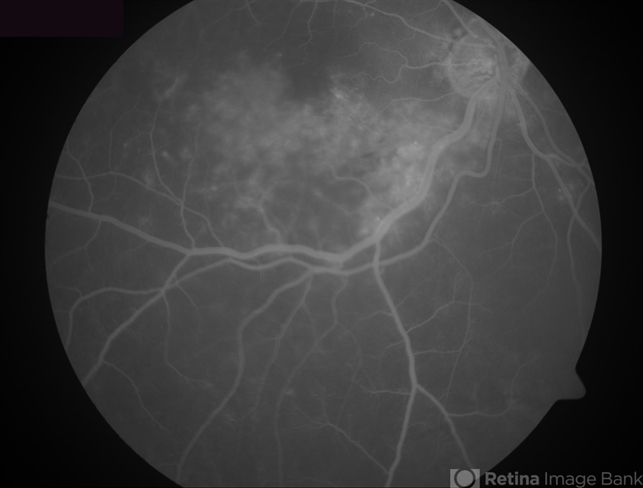

Non-Ischemic Branch Retinal Vein Occlusion With Macular Edema

BRVO with macular edema

Non-ischemic branch retinal vein occlusion with macular edema.